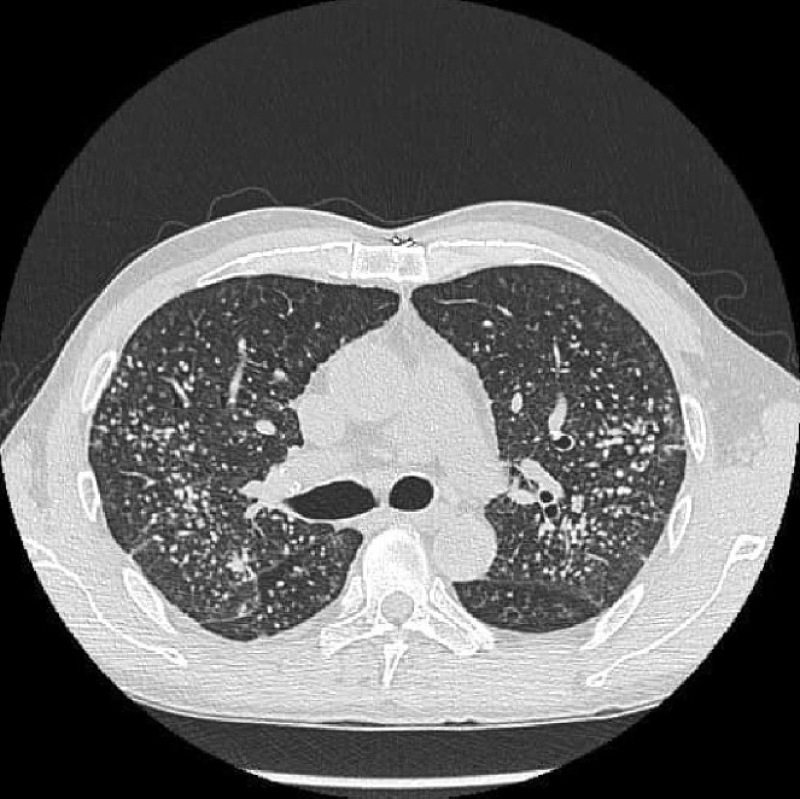

เมื่อทำการเอกซเรย์ปอดก็พบก้อนเนื้อเล็ก ๆ เต็มไปหมด ราวกับท้องฟ้าที่เต็มไปด้วยดวงดาว มีนับพันนับหมื่นจุด ซึ่งอาจทำให้คนที่กลัวสิ่งแออัดรู้สึกขนลุกได้ หากสังเกตเห็นว่านิ้วมือกลายเป็นลักษณะนิ้วตะบอง ควรรีบไปพบแพทย์เพื่อตรวจสอบ ดร.ซู อี้เฟิง กล่าวปิดท้าย